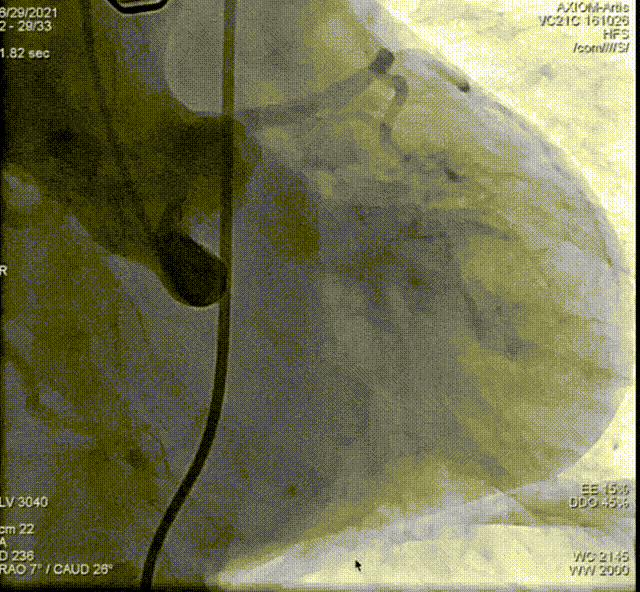

从三叶瓣重度钙化到二叶瓣畸形的根部解剖,从单纯主动脉瓣反流到入路极端迂曲挑战的案例。TaurusOne凭借其优异的柔顺性,支撑力强及内外层双侧裙边的特点,都能从容应对复杂的临床患者解剖结构。从患者的临床选择到术后的长久获益,从手术入路的种类到术中操作的注意事项,从围术期卒中的循证医学到术后的抗凝抗栓用药规范,在线专家共同交流彼此中心的围术期TAVR经验和分享现阶段经导管主动脉瓣置换的诊疗策略。针对当前TAVR领域多个热点学术问题进行了热烈的讨论,现场可谓精彩纷呈、高潮迭起。专家们纷纷借此契机相互交流探讨,分享各自的单中心经验,力求进一步提升TAVR手术的安全性和有效性,为主动脉瓣相关疾病的患者带来长远综合获益。